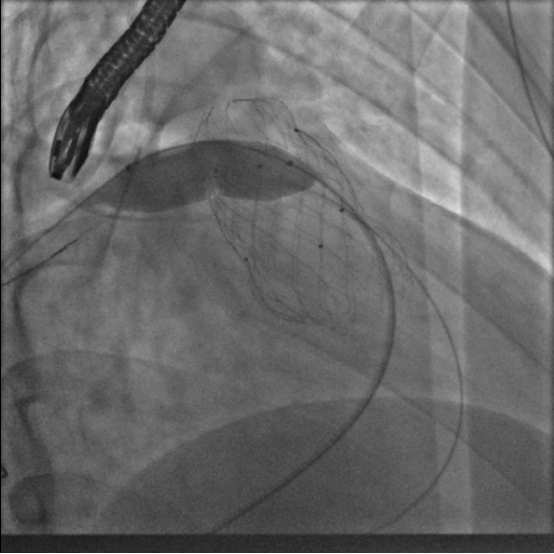

10月12日,葛均波院士、周达新教授团队直播为一名特殊的患者进行TAVR手术,该患者仅有44岁,但因为维持性血透,严重心功能不全,射血分数只有25%,外科医生评估外科手术风险极高,因而转为TAVR手术。

术中由于患者心功能此前已经严重受损,在球囊扩张后由于瓣膜狭窄解除,反流加重出现心脏停跳循环崩溃,体循环血压降至30mmHg以下,周达新主任经验丰富迅速为患者进行胸外按压并同时使用血管活性药物,将患者的血压维持在100mmHg左右,直至其心脏自主收缩恢复。

在瓣膜释放过程中,因为29mm瓣膜太大,患者又是二叶瓣主动脉瓣,导致尽管在瓣膜释放过程中进行快速起搏控制血压,但瓣膜释放过程中数次出现定位困难,一次上弹至升主动脉的过程中,导丝损伤打折,导致瓣膜输送系统与导丝间摩擦力过大,输送系统一时回撤困难,周达新教授用持针器固定导丝,最终成功回撤瓣膜输送系统。但在随后使用6F猪尾巴交替受损的Safari导丝时,因为损伤部位折角过大,猪尾巴管无法通过损伤部位,团队迅速更换6F大腔导管,顺利通过受损导丝到达左心室,使用交换导丝,再上6F猪尾巴管,重新导丝建立轨道。

考虑到瓣膜在释放过程中定位困难,周达新教授在瓣膜释放开始出现下滑后,将瓣膜回收一点后上提紧贴自身瓣膜,再迅速释放,最终使得瓣膜完全固定。因为患者是type0式二叶瓣,瓣膜释放后,支架展开不良,准备予以球囊后扩张,但是食道超声发现左冠窦内可疑有扩碎的瓣叶在飘动。考虑患者的窦部宽大,冠脉堵塞风险较小后还是予以球囊扩张,同时造影看到左右冠血流可。球囊扩张后瓣膜之间展开良好。

虽然手术过程中经历一波三折,但周达新教授沉着应对,团队最终顺利的完成了手术,面对直播镜头,周达新主任及其团队展示了高水平的手术技巧,更展示了强大的心理素质和丰富的手术经验。